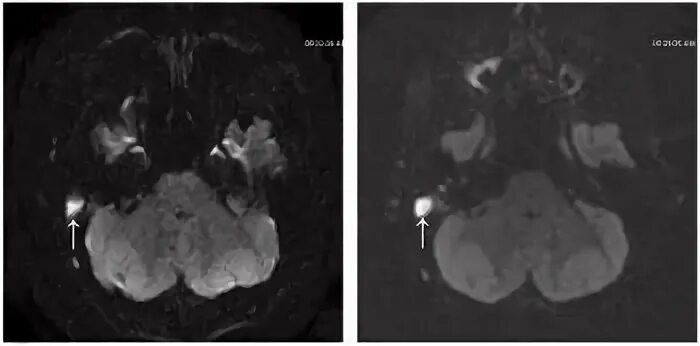

Мрт головного мозга мосто мозжечкового угла